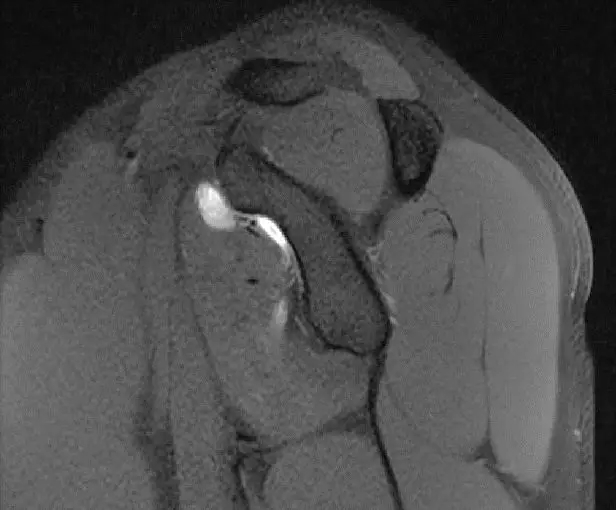

从这个层面可以看到前盂唇,后盂唇,质地均一的T2相低信号,它的前关节囊和后关节囊比较光滑,这是一个比较正常的前后盂唇的形态。

这张片子可以看到上盂唇及肱二头几件长头止点,盂唇高信号的特点,质地比较均一,相对比较尖锐,边界比较清楚